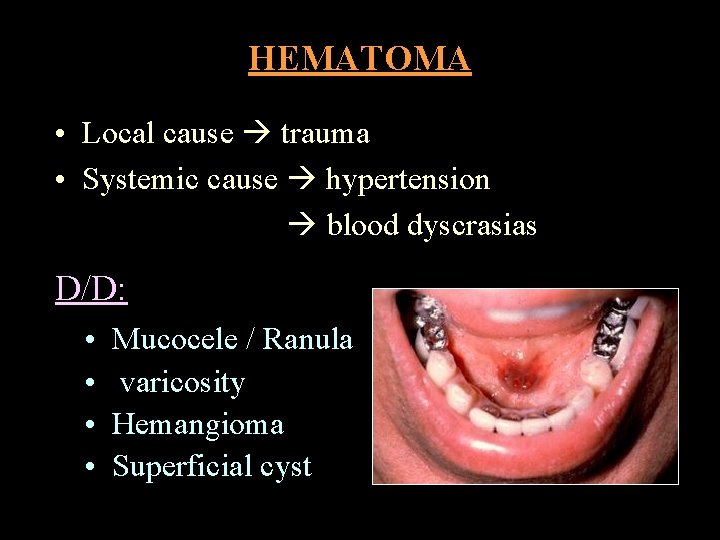

HEMATOMA • Local cause trauma • Systemic cause hypertension blood dyscrasias D/D: • • Mucocele / Ranula varicosity Hemangioma Superficial cyst